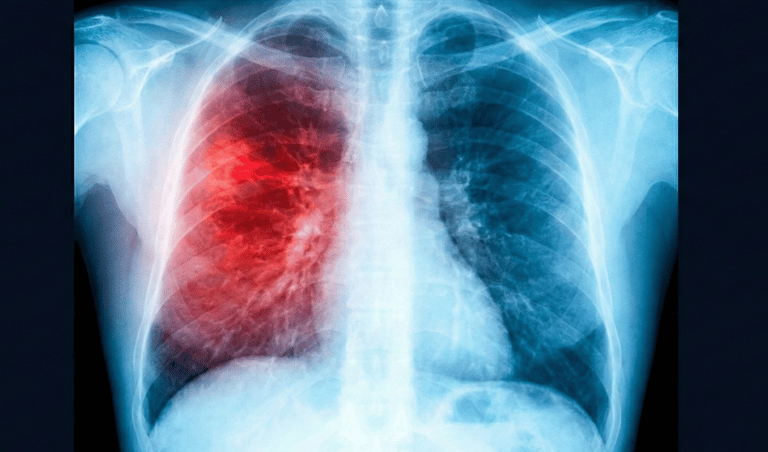

Afectan nariz, garganta, bronquios y pulmones.